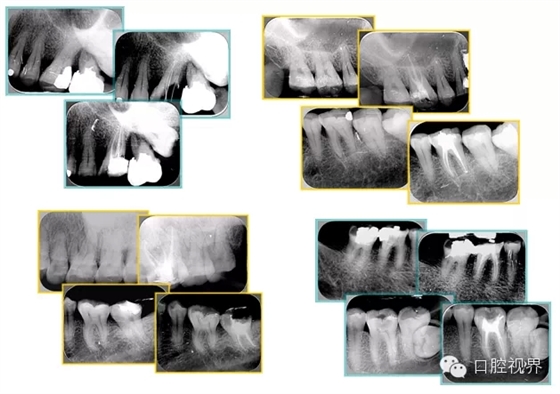

左圖和上圖為干髓治療后牙齒,齲齒疏通后進(jìn)行根管充填。

如圖為塑化加根充處理后牙齒 X 線片。

6. 鈣化

常見(jiàn)有修復(fù)性鈣化和增齡性鈣化。下面為根管鈣化 X 線片。

右圖及下圖為器械折斷的 X 線片。箭頭處示折斷器械。